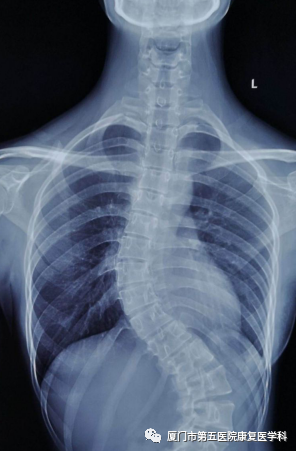

脊柱矫形器:

主要用于固定和保护脊柱,矫正脊柱的异常力学关系,减轻躯干的局部疼痛,保护病变部位免受进一步的损伤。支持麻痹的肌肉,预防、矫正畸形,通过对躯干的支持、运动限制和对脊柱对线的再调整达到矫治脊柱疾患的目的。

侧弯支具矫正